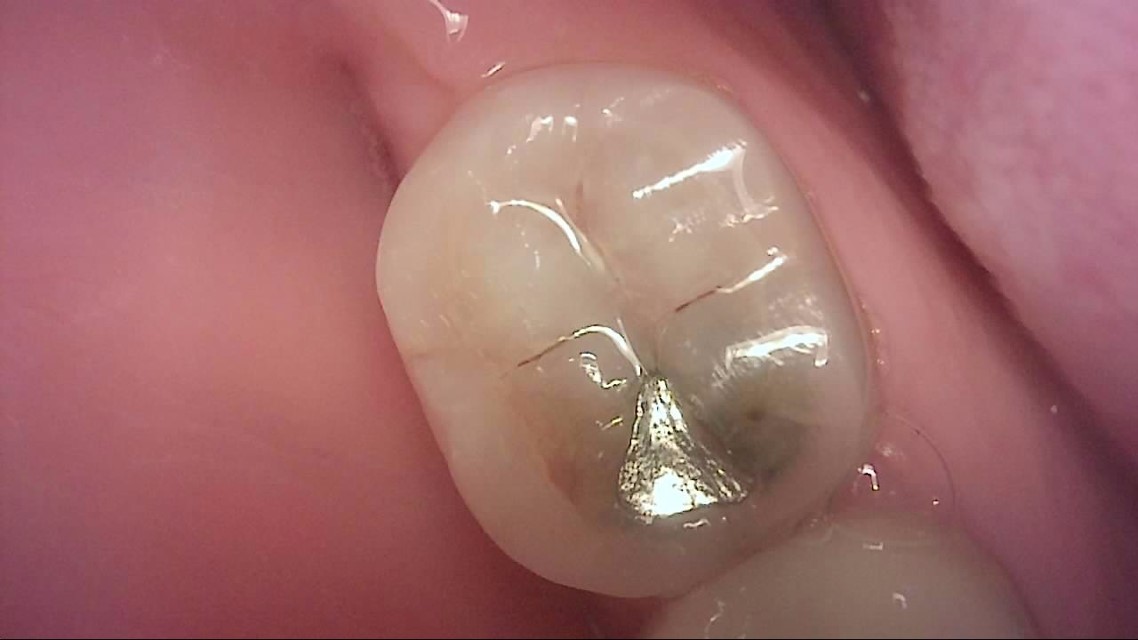

Crack

큐레이캠프로, 큐레이펜씨